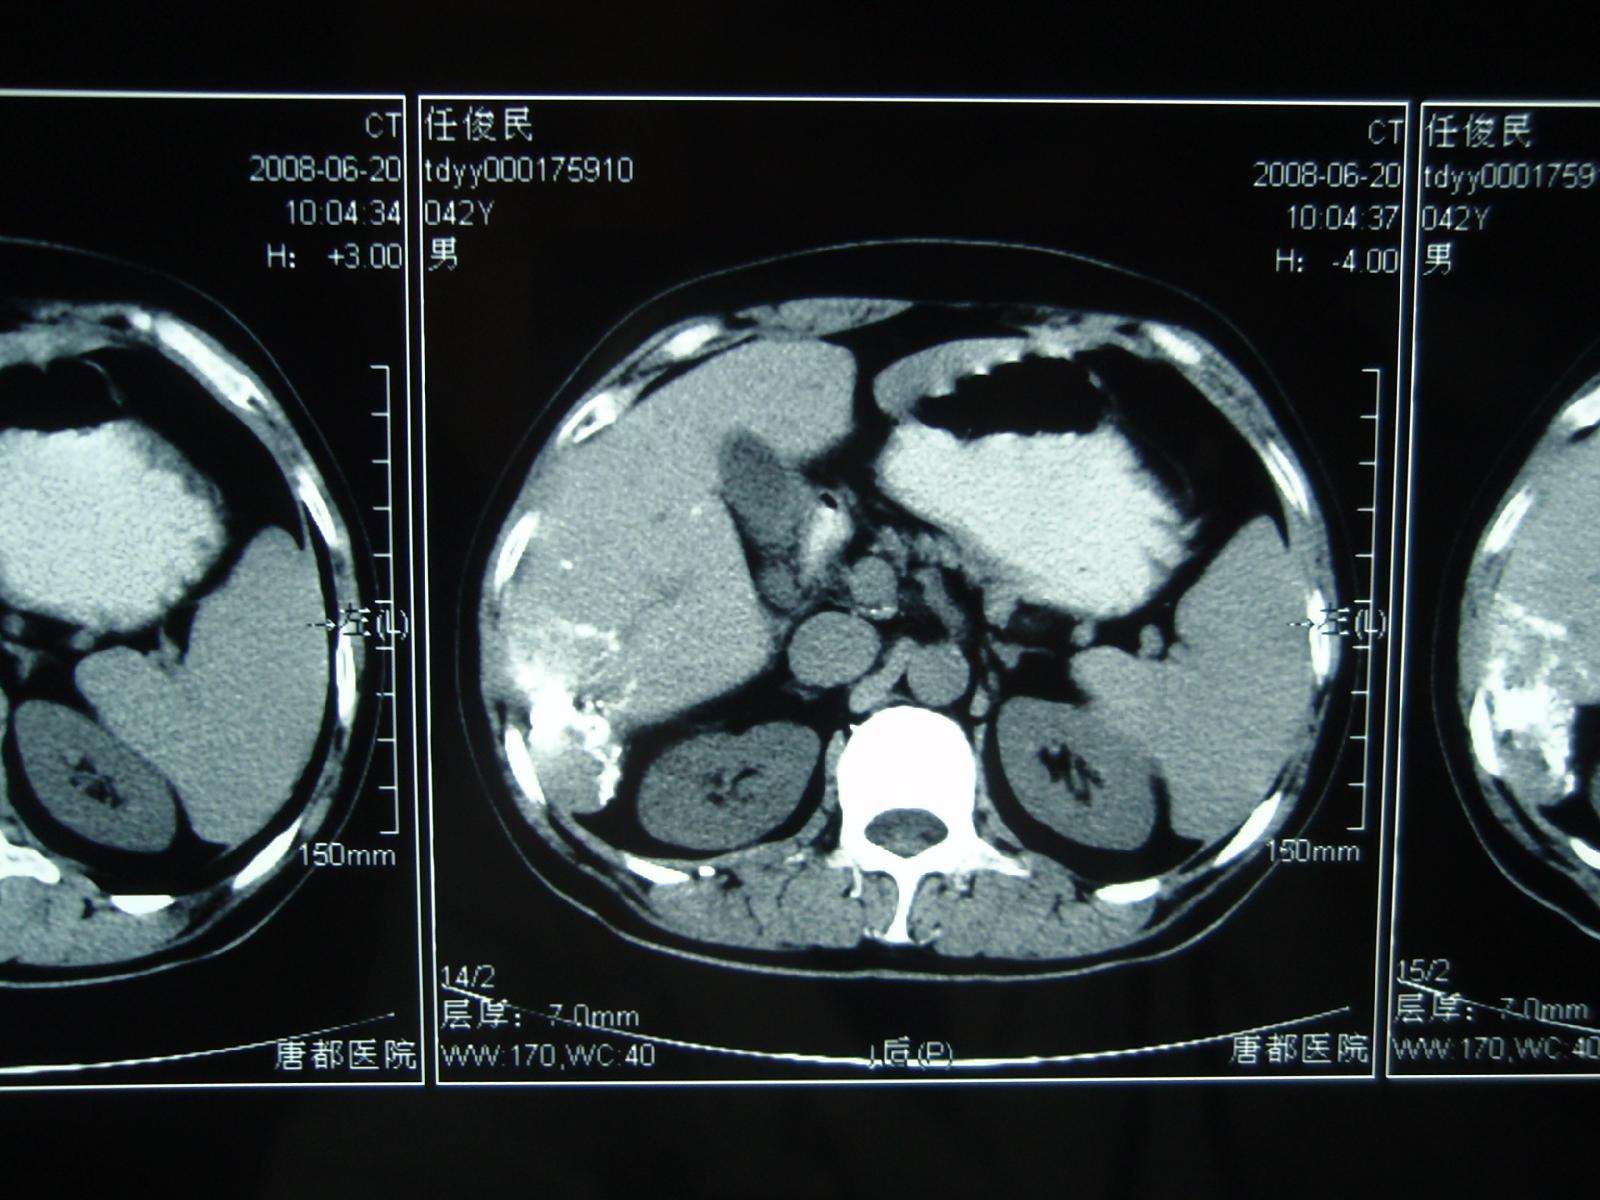

2008年6月20日,栓塞后3个月复查CT显示病灶缩小明显、碘化油沉积良好!